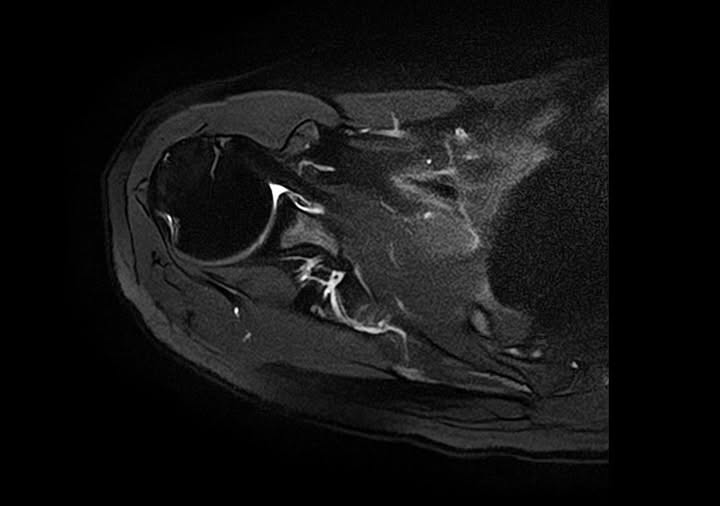

30代女性5年前に転倒して肩関節脱臼をした事を契機に頻繁に肩関節脱臼を繰り返し、当院受診前日に伸びをしただけで肩関節脱臼をしたとの事。

当院に来られた際は通算4回目くらいだったそうで、肩関節の状態を精密検査をして頂く目的で連携先整形外科の肩関節専門医の先生に対診を依頼。

やはり反復性肩関節脱臼で手術になりました。